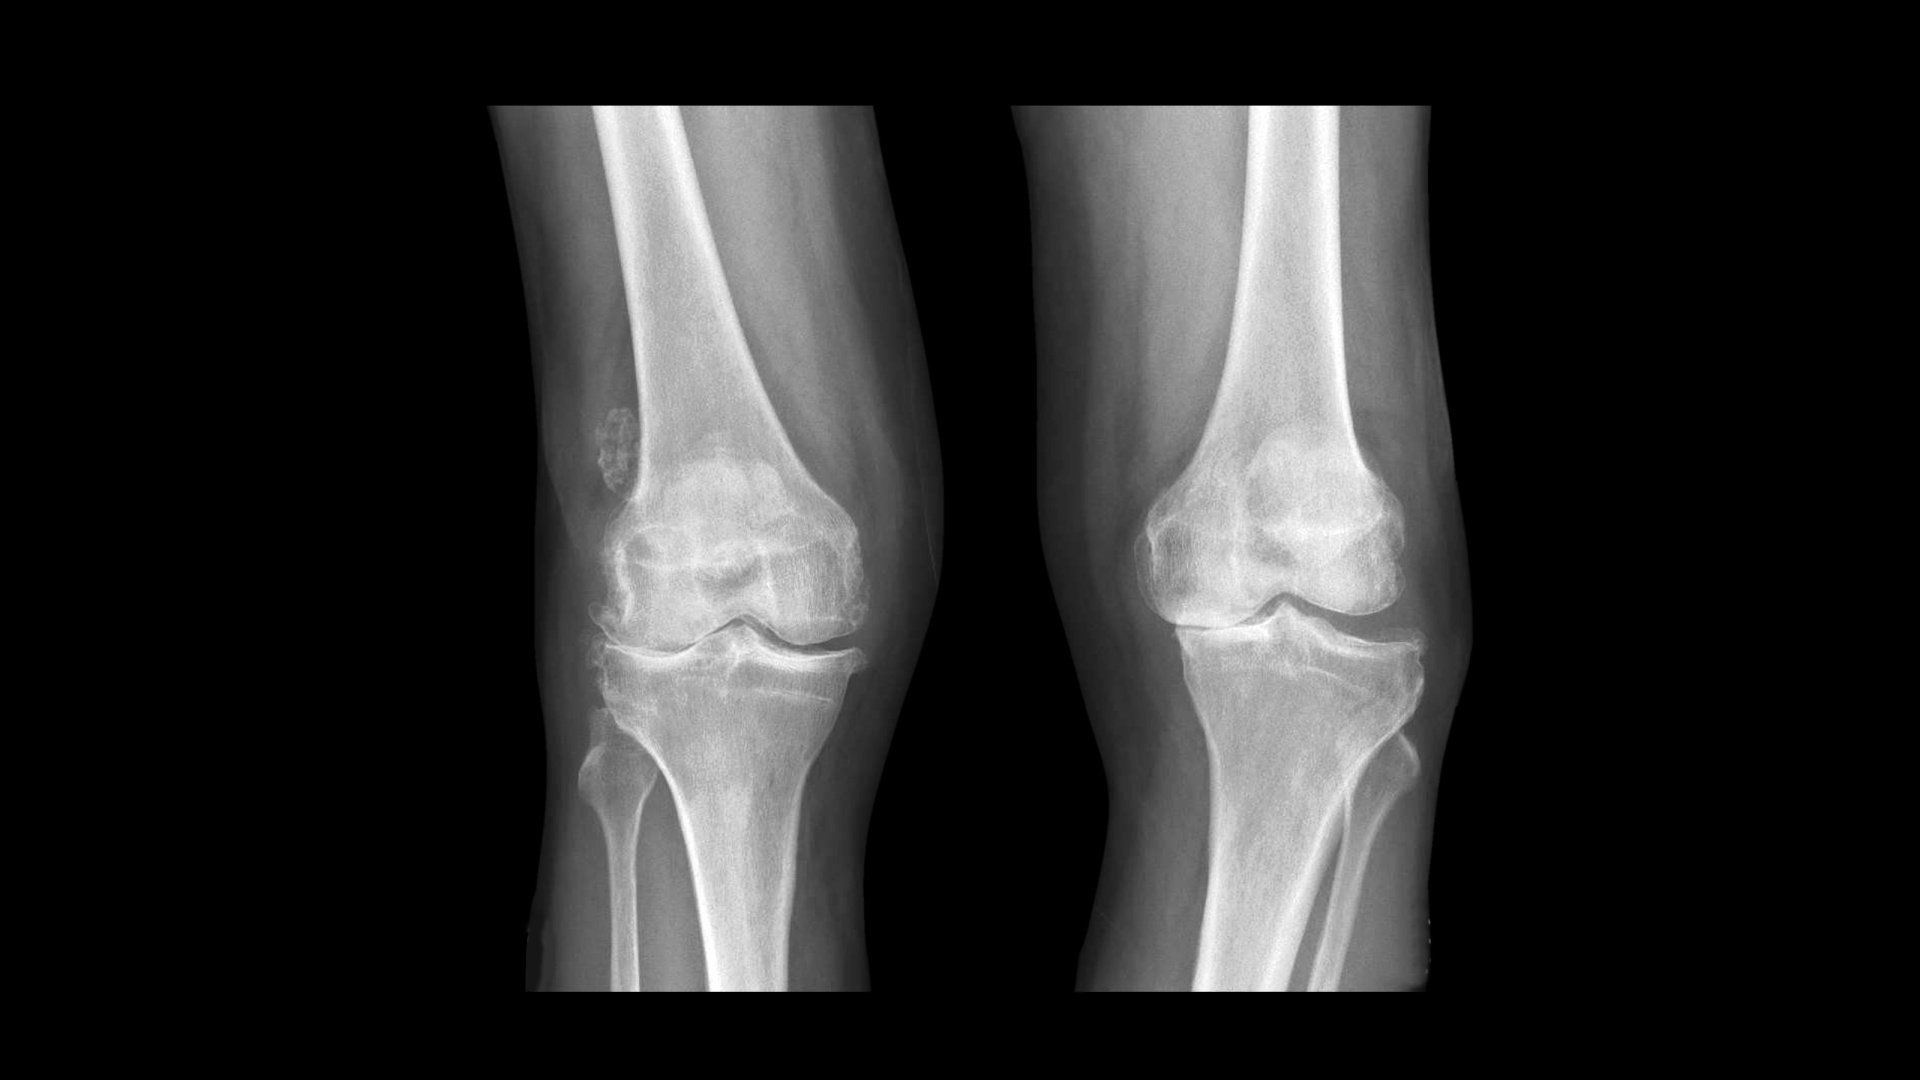

- Η πλευρά της άρθρωσης του γόνατος που εκτίθεται σε αυξημένες δυνάμεις φθείρεται πιο γρήγορα (πρώιμη αρθρίτιδα) και γίνεται επώδυνη

- Ως αποτέλεσμα, περισσότερες δυνάμεις περνούν από την εσωτερική πλευρά του γόνατος, οδηγώντας σε πρώιμη ρήξη του μηνίσκου και του αρθρικού χόνδρου που οδηγεί σε οστεοαρθρίτιδα σε αυτή την πλευρά του γόνατος

- Είναι ο συνηθέστερος τύπος παραμόρφωσης του γόνατος γι’ αυτό και παρατηρείται οστεοαρθρίτιδα πιο συχνά και πιο έντονα στην έσω πλευρά του γόνατος

- Ως αποτέλεσμα, περισσότερες δυνάμεις περνούν από την έξω (εξωτερική) πλευρά του γόνατος, οδηγώντας σε πρόωρη βλάβη του μηνίσκου και του αρθρικού χόνδρου που οδηγεί σε οστεοαρθρίτιδα έξω διαμερίσματος